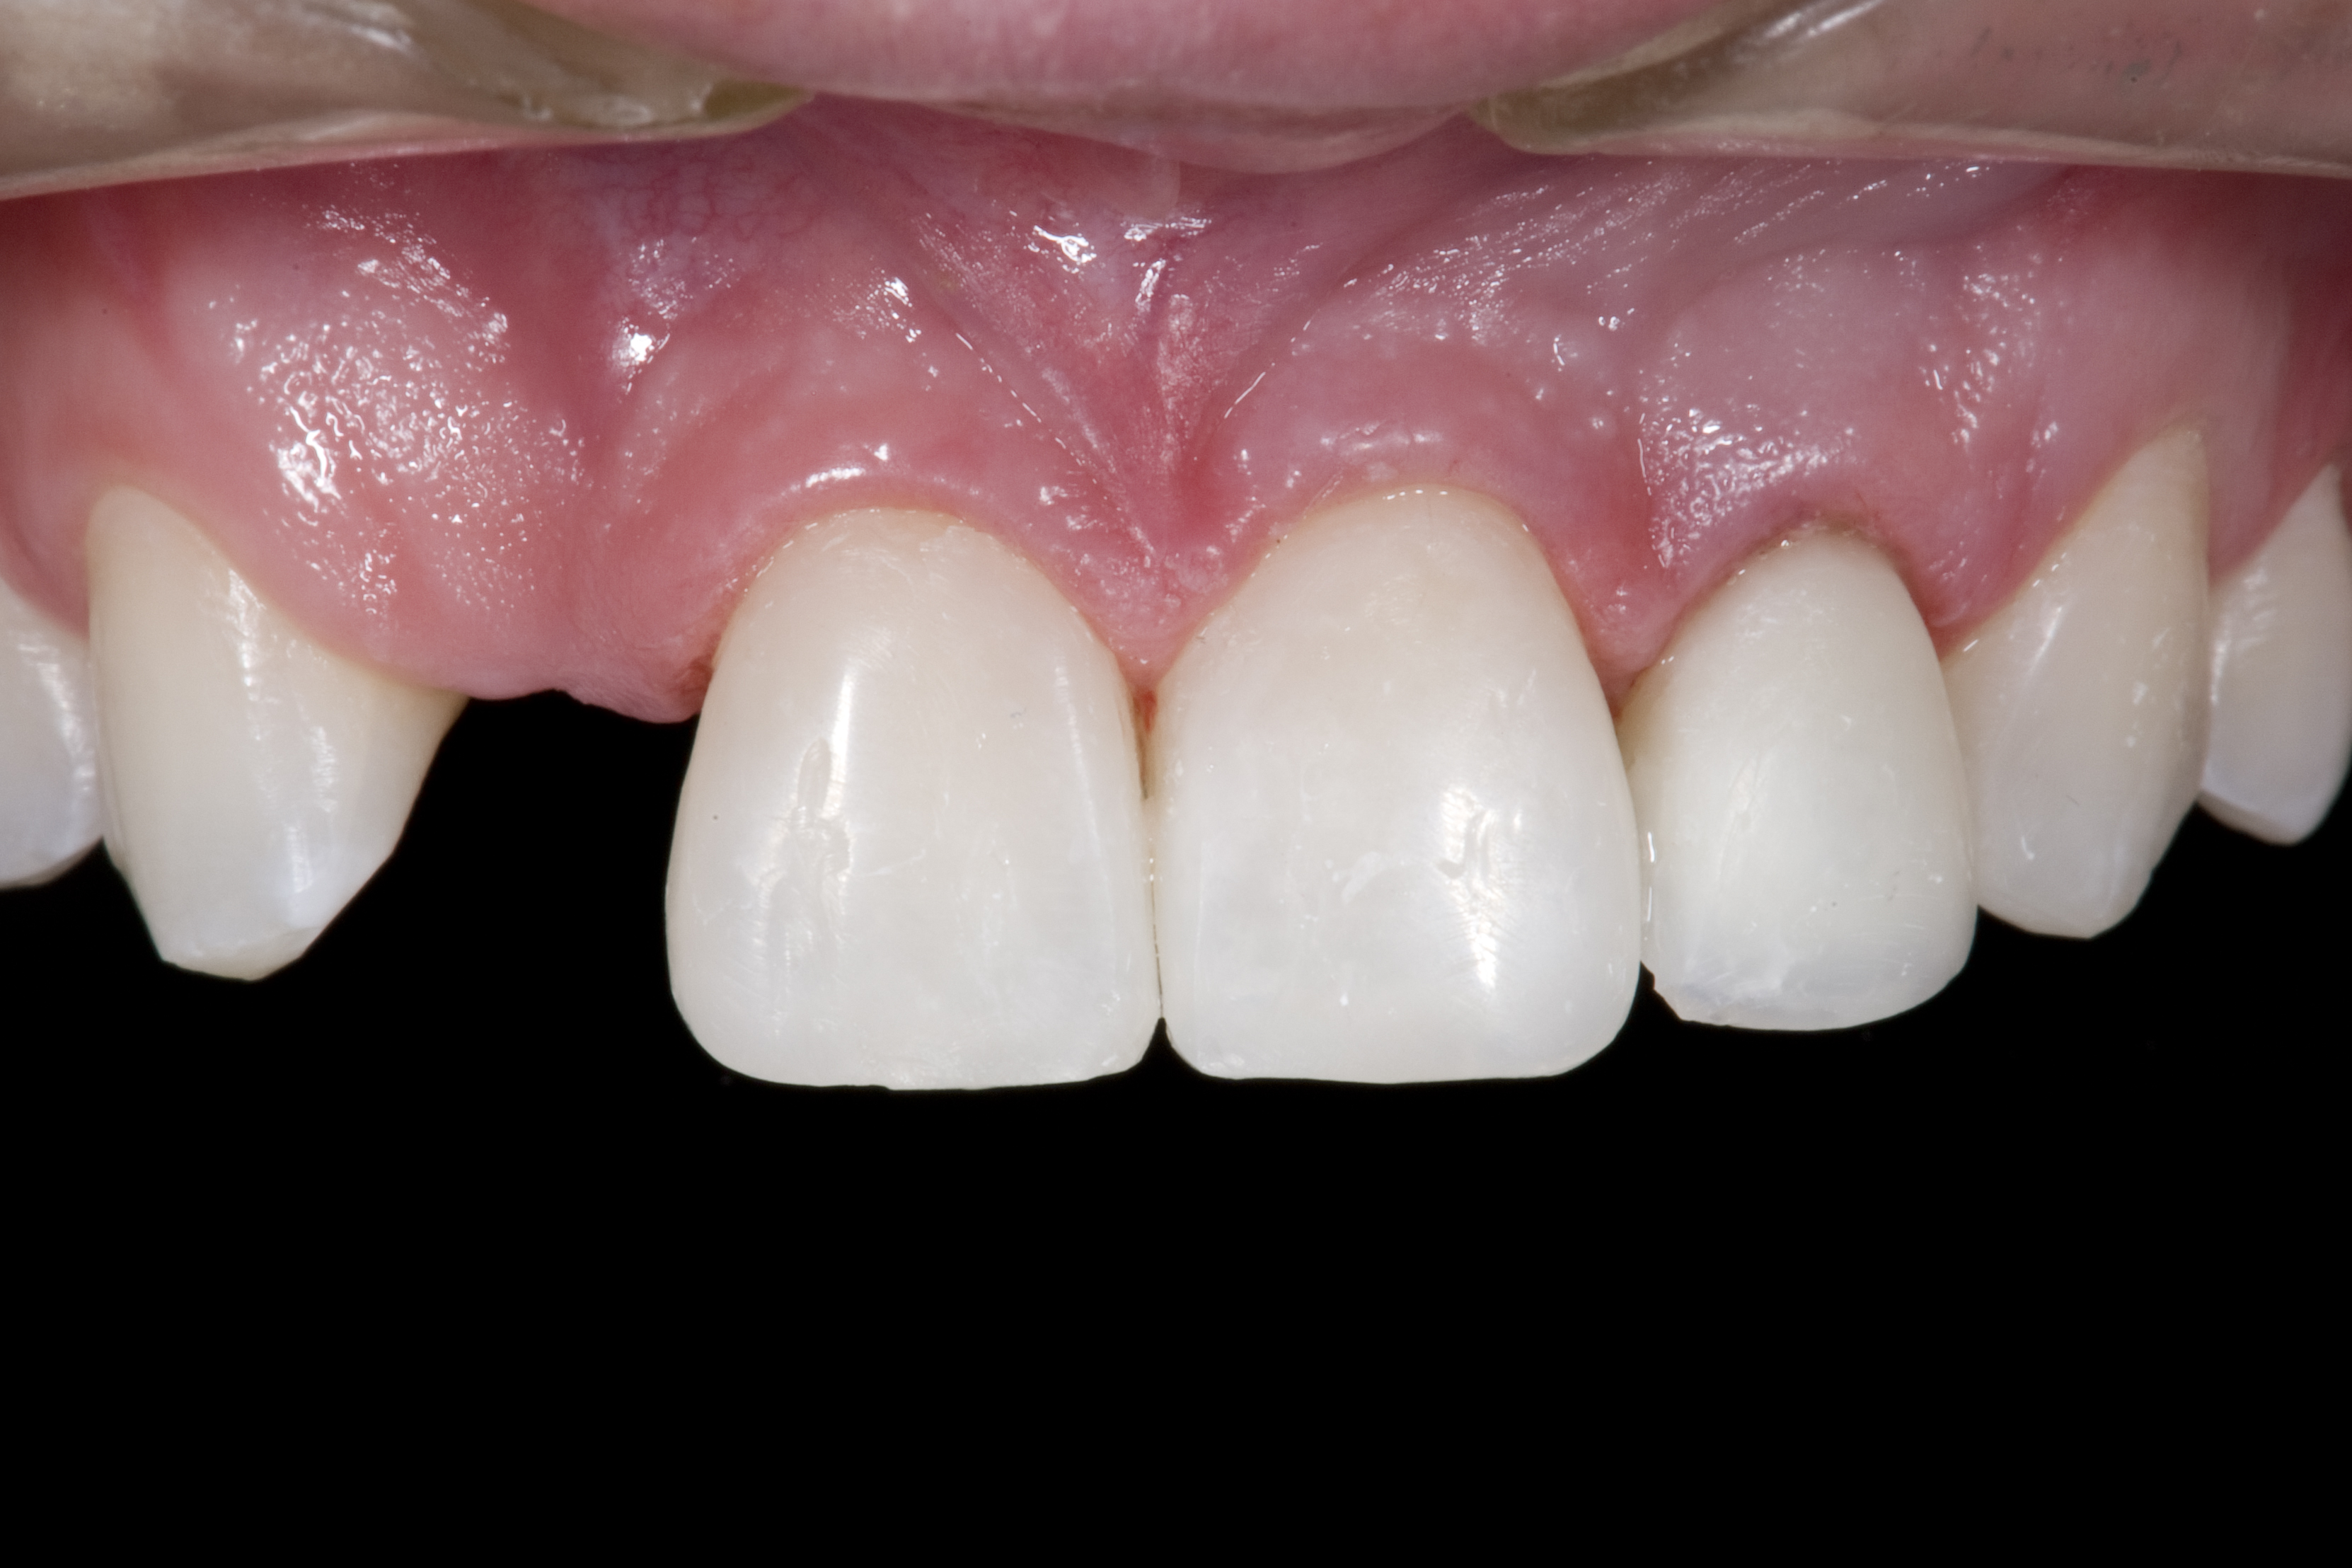

(4.) Double-wing metal resin-bonded (Maryland) bridge replacing the right lateral incisor (facial view).

Figure 4

A 14-year-old patient presented to the office with his mother (Figure 1). His chief complaint involved the large spaces between the teeth created by his missing right maxillary lateral incisor and his small left maxillary lateral incisor. He desired to replace the missing tooth with an implant and create a beautiful smile. Upon examination, he was found to have a class I canine and molar relationship, but because he had a tooth size/arch size discrepancy and space distal to the right central incisor, the remaining incisors had drifted to the right. The left maxillary lateral incisor was peg-shaped and in a cross bite position. Studies have shown a clear association between congenitally missing teeth and reduced tooth size.59-62 Because he was only 14-years-old at the time and could not have implants placed until the cessation of growth (somewhere in the vicinity of 22 years old), he was sent to the orthodontist for alignment of the teeth.16,17 After 2 years of orthodontics, the appliances were removed, and his tooth coloration was improved using carbamide peroxide bleaching (Figure 2). Because some form of provisional needed to be placed until he was finished growing, a double-wing metal resin-bonded bridge was chosen. As discussed earlier, this is the ideal transitional prosthesis for patients that have congenitally missing maxillary lateral incisors. The benefits of this type of prosthesis include its ability to be removed and rebonded during the surgical phase of treatment and its ability to retain the roots in their proper position after orthodontic treatment.16 The final plan for the patient was to increase the width of the central and the maxillary left lateral incisor, utilizing porcelain laminate veneers to achieve the appropriate width/length ratio of 80%. A wax-up was created to idealize tooth size, a putty matrix was made from the wax-up to facilitate bonding of the incisors, and a non-precious, double-wing metal resin-bonded bridge was fabricated for lateral incisor replacement. Once the teeth were bonded to ideal size, the “Maryland Bridge” was fabricated from a polyvinyl arch impression with the newly bonded teeth (Figure 3). The metal frame was cast from a non-precious alloy to allow for fabrication of a very thin frame and to create a better surface for bonding. After sandblasting the internal aspect of the frame with CoJet™ silica (3M ESPE), accomplishing salinization, and executing cementation with a dual-cure resin cement, a fairly good adhesion to the frame was anticipated.29 The enamel surface was etched with phosphoric acid for 30 seconds, the primer (Single Bond Plus, 3M ESPE) was applied to both the internal surface of the sandblasted framework and the etched enamel, and the bridge was cemented with RelyX™ ARC (3M Espe) dual-cured resin cement (Figure 4 and Figure 5).